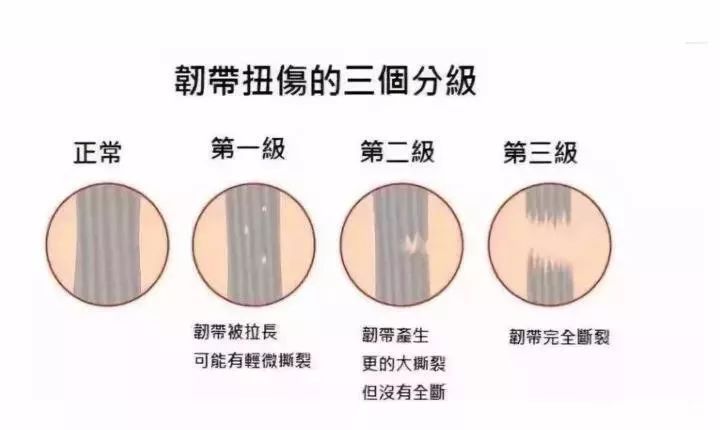

医生:需不需要打石膏,这得根据不同情况来定。如果是骨折,那就没有商量的余地,必须石膏固定,甚至需要手术治疗。如果是踝关节外侧韧带损伤,那就得看损伤的程度。我们一般将外侧韧带损伤分为3级。1级就遵循rice原则,1周左右肿会消退;2级韧带部分断裂,通常需要3-6周,甚至数月才能完全恢复;3级韧带完全断裂,可能会存在关节持续失稳,恢复不好的话可能要手术治疗的。所以2级、3级我们都需要打石膏。